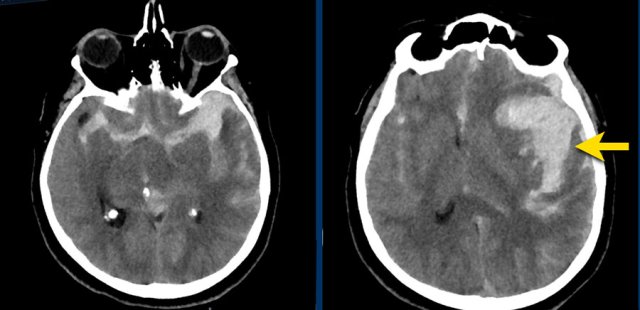

Right lower image is venous infarction due to sinus thrombosis (yellow arrows) Right lower image is venous infarction due to sinus thrombosis (yellow arrows)

When an aneurysm ruptures the pressure of the jet can be so high, that the blood will be injected into the brain parenchyma as can be seen in this example.

This patient presented with a subarachnoidal haemorrhage due to an aneurysm in the anterior communicating artery.

There is also an intraparenchymal heamatoma in the right gyrus rectus (arrow).

NCCT shows bilateral subarachnoid hemorrhage  and a parenchymal hemorrhage (yellow arrow).

CTA show at the location of the parenchymal hemorrhage a flow related aneurysm of the anterior communicans artery, which was considered the cause of the SAH.

Notice the hemorrhage next to the aneurysm (circle).